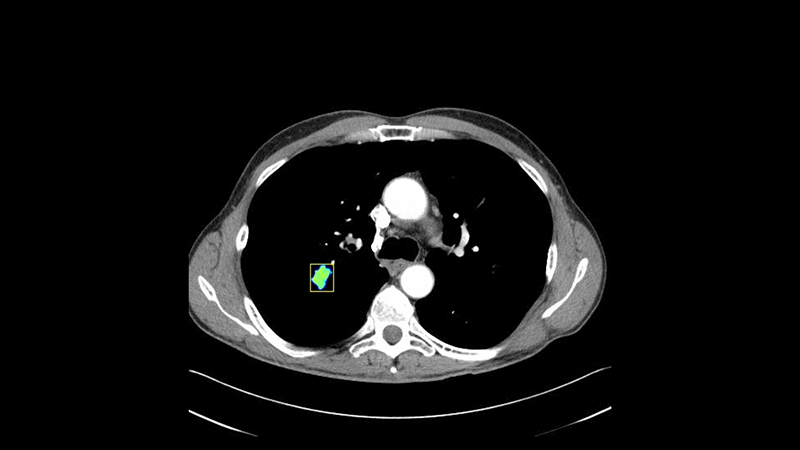

First, advanced computer vision capabilities built with deep learning algorithms assess the malignancy risk of pulmonary nodules based on factors such as nodule size, shape, density, volume, as well as patient demographics such as years smoking, age, gender, and race. “We want to be able to take any clinical input such as a radiology test, lab test, or personalized clinical variables and say here is the likelihood of a disease state and provide output on utility and management of next steps, and that’s our goal with deep learning,” said Dr. Alzubaidi.

Five distinct classes of machine learning models are applied to cancer risk assessment in order to account for the distinct classes of nonlinearities that could be hiding in the data. Four distinct classes of features are auto-extracted directly from the images using a set of computer vision algorithms.

The Matrix Analytics tools were able to outperform previous methods in their ability to diagnose cancer from a CT image. And compared to conventional methods, deep learning requires no hand-tuned feature extractor, making the process much more independent.